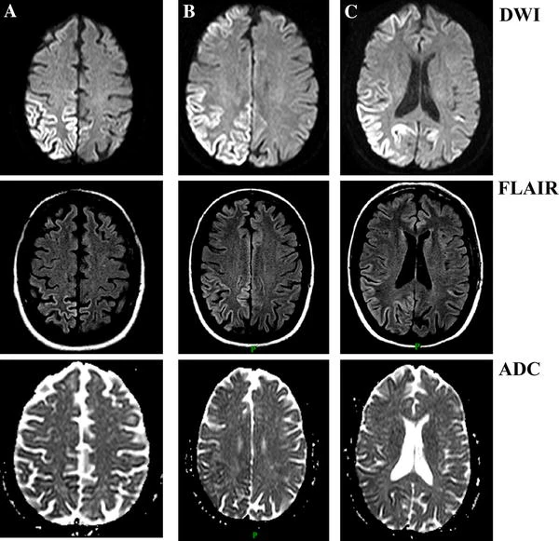

克雅病(cjd)

图片尺寸640x387